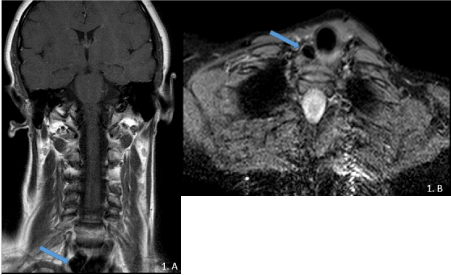

Figure 1.A)Coronal T1 TSE –MRI of the neck and B) axial STIR at the level of the

thoracic cervical junction. A hypointense lesion, well defined, right paratracheal was observed (blue arrow).